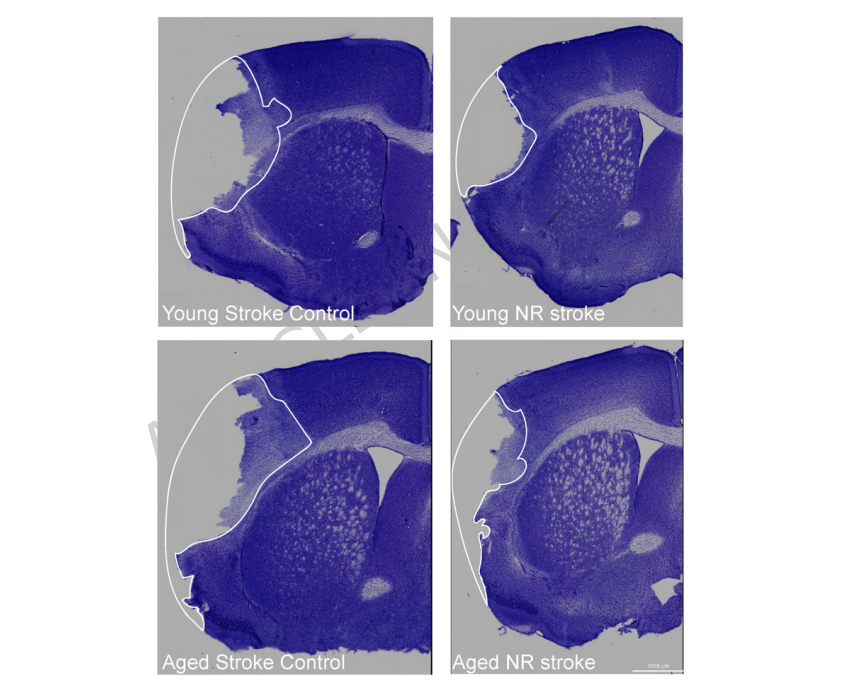

改善神经功能结局

在功能层面,NR处理显著改善了老年中风小鼠的运动协调能力,减少了脑梗死面积。这一效果可能源于多系统的协同作用:通过改善外周免疫细胞代谢、减轻系统性炎症、保护肠道屏障,最终降低神经炎症负担。